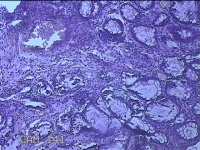

性别

男

年龄

40岁

临床诊断

混合痔

一般病史

反复肛门肿物突出15年。

标本名称

肛门肿物

大体所见

灰白暗红色肿物0.7x0.5x0.2cm一个,表面糜烂。

脱水、透明,浸蜡、脱蜡效果不佳,制片质量差。